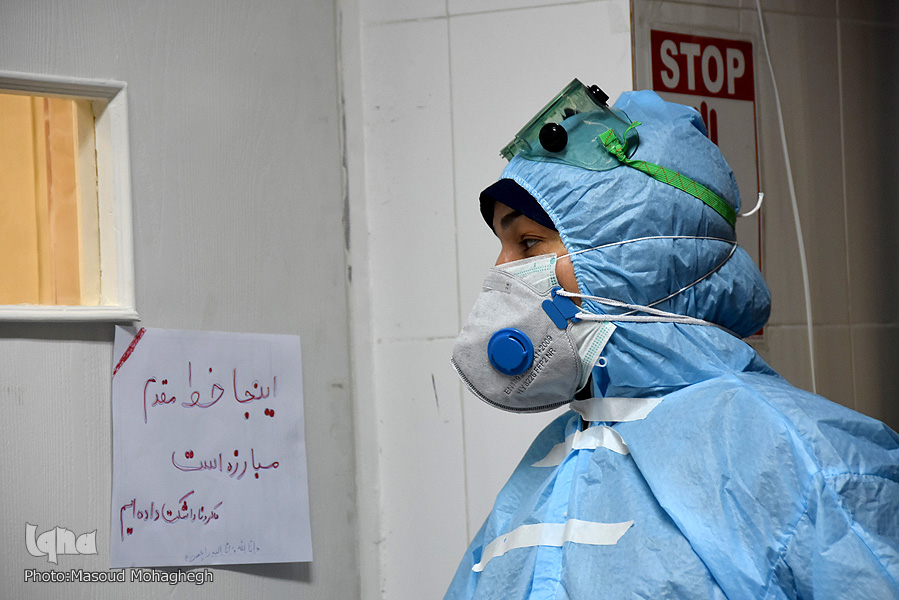

خاطرات کرونایی یک پزشک؛

نبضهای کُند و نفسهایی که به شماره میافتاد

یک پزشک مشهدی گفت: سختترین لحظات روزهای کرونایی وقتی بود که نفسهایمان با کُند شدن نبض بیماران به شماره میافتاد.